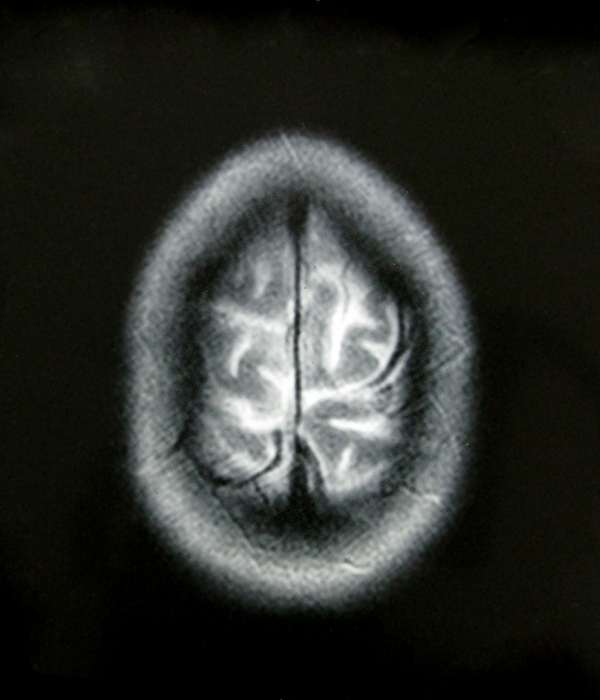

- My Brain in 2009